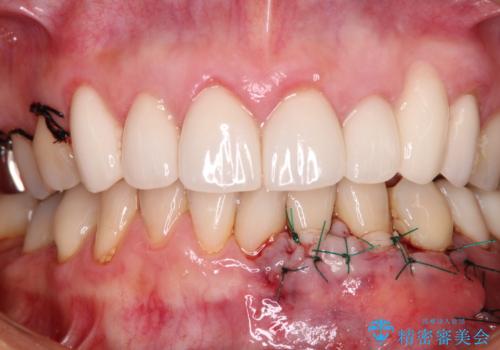

- 今まで知覚過敏の薬や歯磨き粉などを散々試しても全く改善されないとのことで来院された患者様です。

歯根面が露出しており、少し風をかけるだけでもしみてしまう状況でした。

セラミッククラウンによる治療も検討されていましたが、歯肉が非常に薄く、クラウンを装着しても将来的に歯肉退縮を起こす可能性が考えられたので、まずは歯肉移植による根面被覆を行うこととしました。

外科処置に恐怖心があるとのことで、移植手術を行う際には、静脈内鎮静法にてリラックスした状態で処置を受けていただきました(別途税別5万円)。